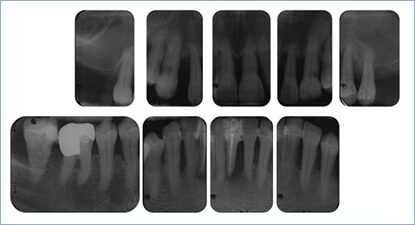

DermanIm Röntgenstatus (Abb. 5) zeigte sich ein generalisierter horizontaler Knochenverlust mit deutlichen Niveauunterschieden von 20 bis 80%. Die Sextanten mit dem größten horizontalen Knochenabbau waren der zweite mit 60 bis 80% und der fünfte mit 50 bis 80%. Vertikale Knochentaschen lagen an Zahn 15 (distal 2 bis 3 mm), an Zahn 22 (mesial 2 mm), an Zahn 24 (distal etwa 3 bis 4 mm), Zahn 45 (mesial und distal je 1 bis 2 mm) und an Zahn 47 mit einem schüsselförmigen Defekt im unteren Wurzeldrittel vor. Zahn 41 zeigte bei bestehender zementdichter Verschattung im Wurzelkanal eine periradikuläre Aufhellung. An Zahn 46 war ein radiologischer Furkationsbefall zu sehen. Einen verbreiterten Parodontalspalt wiesen die Zähne 22 (mesial und distal), 34 (mesial und distal) und 45 (mesial und distal im koronalen Wurzelviertel) auf. Röntgendichte Ablagerungen auf den Wurzeloberflächen waren nicht zu finden. Aus den Anfangsbefunden ließen sich folgende Diagnosen ableiten:

- generalisierte Parodontitis Stadium IV Grad C, Falltyp 2 und 3 [2,10]

- sekundäres okklusales Trauma mit Auffächerungen der OK-Front und Auslenkung der Zähne 12 und 22 in Zentrik [11]

- nicht erhaltungswürdige Zähne 41 und 47